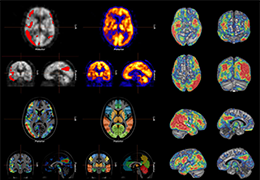

View X-Ray CT & MRI Scans Fast and Easily

FREE and easy to use 3D DICOM Viewer – for surgeons and patient education

Designed for surgeons, Pro Surgical 3D makes it easy to view patient scans quickly. Pro Surgical 3D facilitates the optimal 3D treatment and assessment workflows based on X-ray CT and MRI scans – and best of all, it’s FREE!

Everyone – including surgeons, patients and their loved ones – benefits from being better informed by the wealth of information buried within CT and MRI scans. Pro Surgical 3D gives surgeons more information to develop optimal treatment plans for patients. It also helps patients and their support group better understand their medical condition and proposed treatment options.

High-quality and fast 3D reconstruction and 3D rendering

Performs 3D reconstruction and volume rendering.

Multi-planar slicing.

Side-by-side comparative assessment for pre- and post-operative scans.